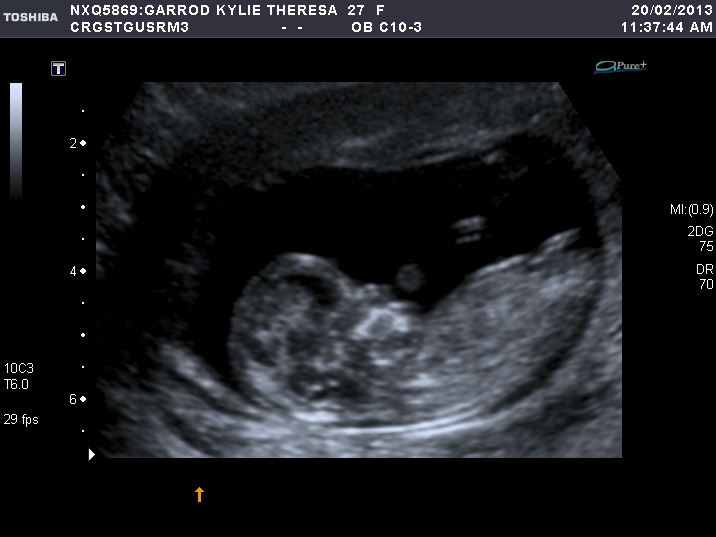

3rd I thought girl

I'm going to say boy for the 1st & 2nd picture definetly, but the 3rd picture throws me somewhat!